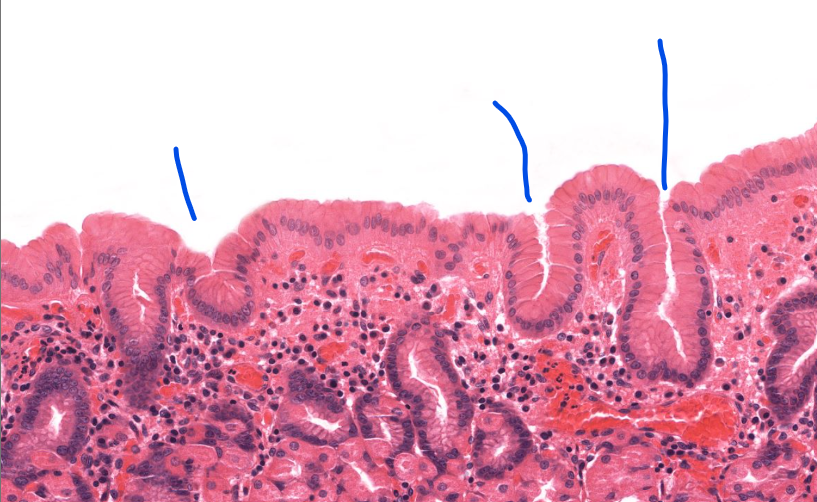

gastroesophageal junction

notice the shift from strat squamous to simple columnar (with long linear/coiled glands)

tissue type

simple columnar epi of the stomach

layer

adventitia